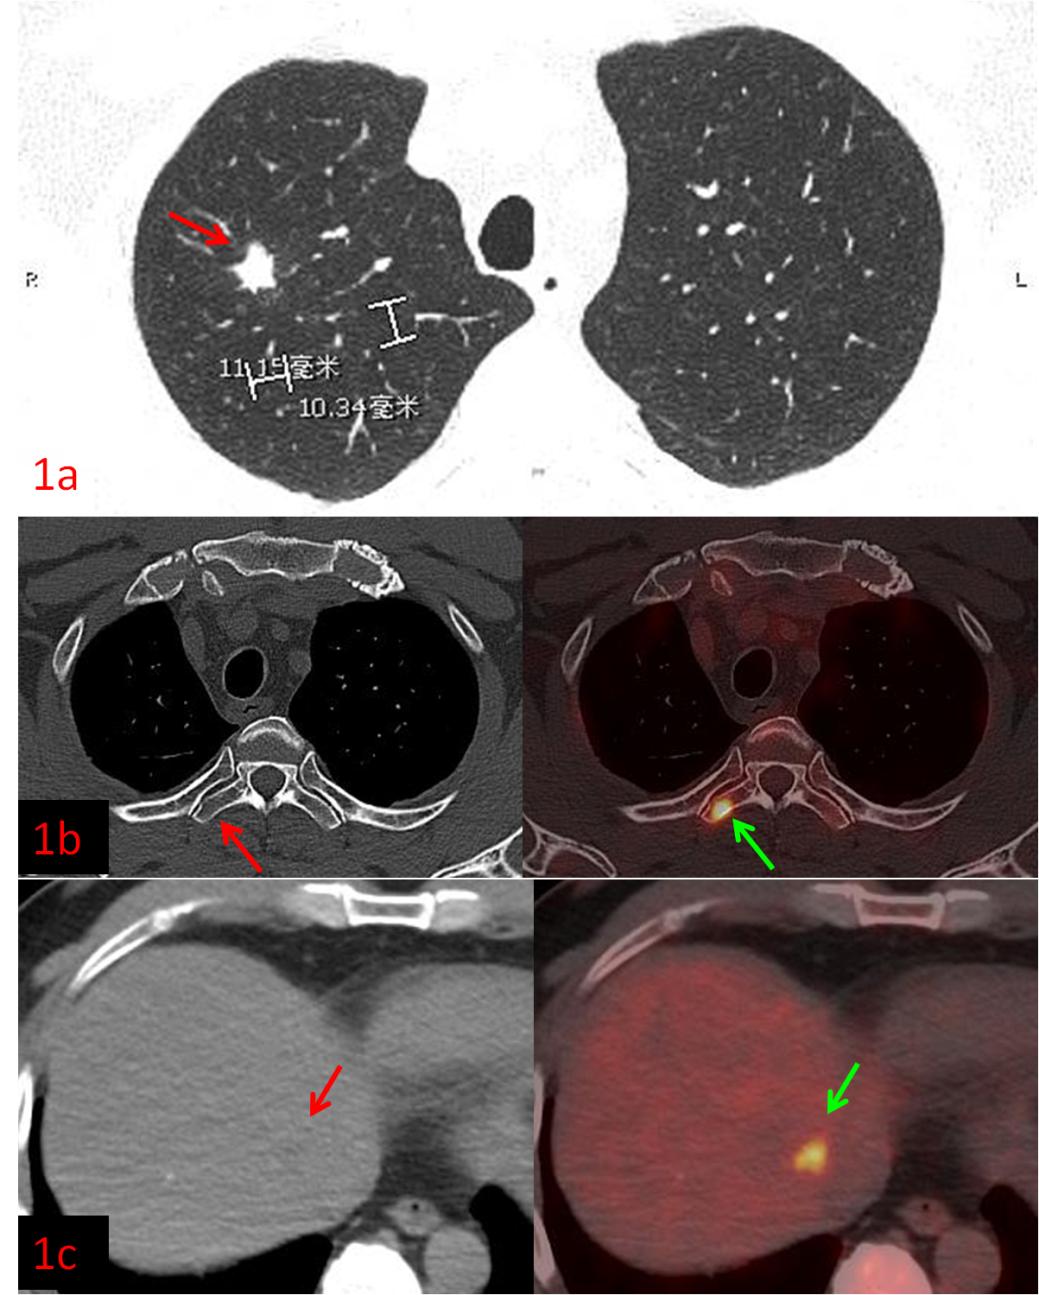

例1:中年男性,CT發現右肺上葉結節,1.1cm×1.0cm,余未見異常,這時候患者初步分期應該是ⅠA期,屬于早期肺癌,可以行根治性手術。而PET/CT檢查示:肝臟、多發骨骼轉移,這時候分期直接跳到ⅣB期,屬于晚期肺癌,不適合手術,可以根據病理、基因檢測結果選擇合適的藥物治療或聯合治療方案,避免了無效的手術創傷。病理:浸潤性腺癌。